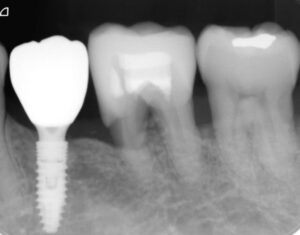

レントゲン写真を撮影すると、隣の第1大臼歯は重度の歯周病になっていたため、抜歯の後に2本のインプラントを検討すべき状況でした。

患者様の願いが天に通じたのか否かはわかりませんが、予想以上に歯周組織再生治療の効果が発現し、無事にインプラント治療を行うことができました。

患者様は相変わらずヘビースモーカーのままですが、歯磨きの状況は申し分なく、定期健診にも積極的に応じています。